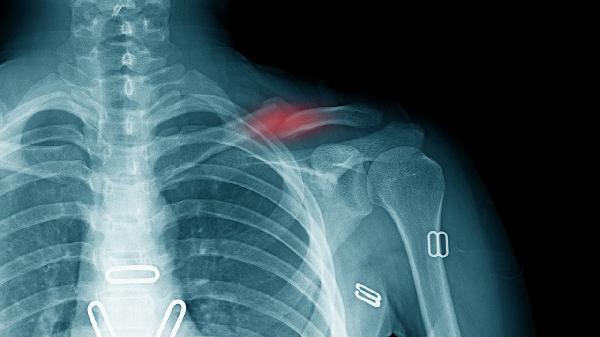

左肱骨中段骨折可通过手法复位外固定、石膏固定、支具固定、切开复位内固定、康复训练等方式治疗。左肱骨中段骨折通常由直接暴力、间接暴力、骨质疏松、病理性骨折、运动损伤等原因引起。

手法复位外固定适用于无明显移位的左肱骨中段骨折。医生通过手法将骨折端复位后,使用夹板或石膏托进行外固定。复位后需定期复查X线片观察骨折对位情况。固定期间避免患肢负重活动,防止骨折再次移位。固定时间通常为4-6周,具体时间根据骨折愈合情况决定。

切开复位内固定适用于严重移位或不稳定的左肱骨中段骨折。手术常采用钢板螺钉内固定或髓内钉固定,术后早期可进行功能锻炼。内固定物通常需要12-18个月后取出,具体时间根据骨折愈合情况决定。术后需预防感染,可静脉滴注注射用头孢呋辛钠。康复期需加强营养,补充钙剂和维生素D。